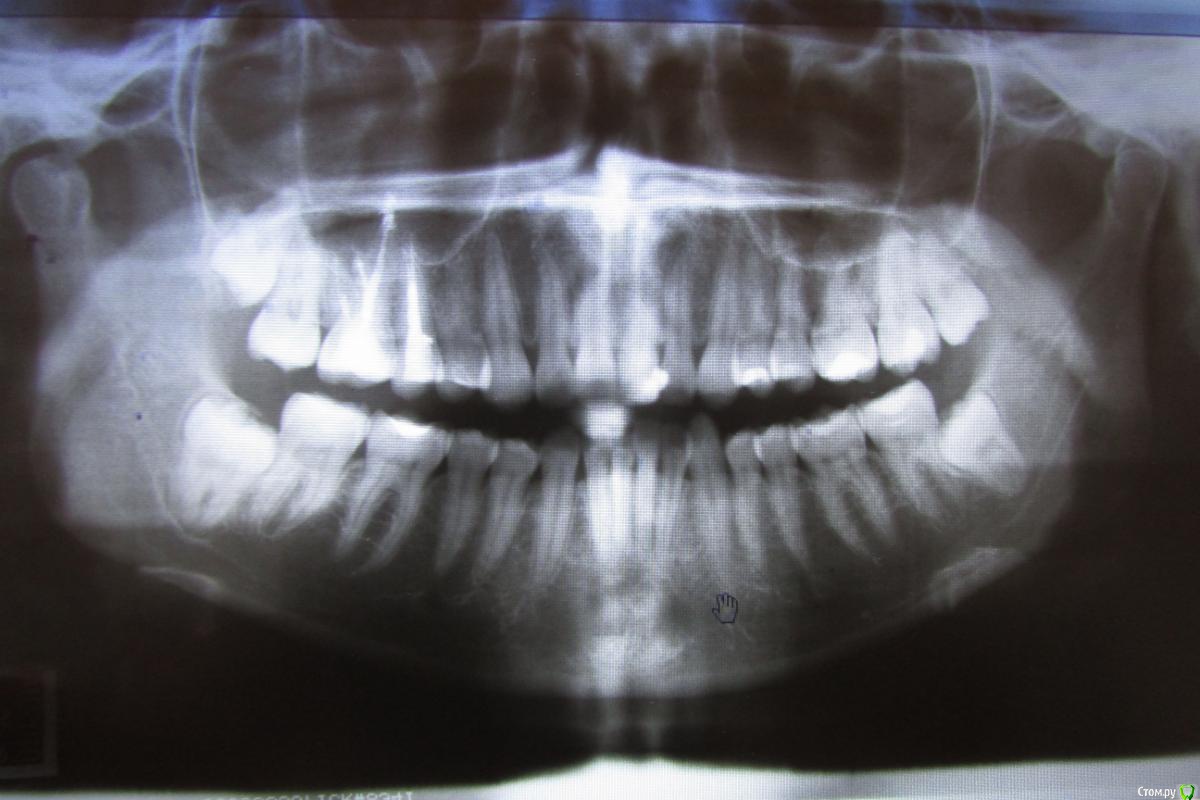

pustoe Опубликовано 13 марта, 2016 Автор Поделиться Опубликовано 13 марта, 2016 Уважаемые врачи, помогите советом! После тройного перелечивания 25 зуба я пол года не обращала внимания на то что чувствую боль при надкусывании. Но надоедает, знаете ли. Ещё раз попыталась понять точно ли 25 болит и выяснила, что боль в 26 зубе. Только при давлении на 1 определённый участок. И боль возникает только при жевании или когда я самостоятельно зубами пытаюсь найти этот участок. На осмотре зуб никак не реагирует ни на давление, ни на воздух, ни на холодную воду. Ну и главное - он мёртвый. Год назад обратилась в клинику, где проводили депульпирование зуба. На снимках врач не нашёл патологий, при ощупывании десны заметил боль в области 28 зуба. Хороший снимок 28 сделать не получилось, направили к хирургу.Посетила хирурга, сделали 3д-томографию. Хирург сказал, что удалять 28 зуб не нужно и проблема в 26, на снимке видна гранулёма. Ниже приложила 2 снимка от хирурга (декабрь 2014 г.). Обратилась в ту же клинику, где лечила 26 зуб , попросила 1) сменить врача, 2) лечить по гарантии. Зуб пролечили (февраль 2015 г.), результаты лечения на снимке №299 (сделан в ноябре 2015 г). Боли при надкусывании появились спустя недели 2-3. Далее в связи с переездом в другой город, не было возможности вновь обратиться к лечащему врачу, поэтому обратилась в новую клинику с целью удалить зуб или наткнуться на профессионалов, которые вылечат меня. В ней посчастливилось услышать аж два мнения разных врачей: терапевт сказал, что все дураки и плохо меня пролечили, надо заново перепломбировать каналы и закладывать лекарства, плюс на 25 зубе обнаружил гранулёму (осмотра физически не произвёл в связи с тем, что на час задержал мой приём и за мной был другой пациент, поэтому времени на меня у врача не было). Второй врач-пародонтолог предложил сделать резекцию. Я согласилась на второй вариант, при посещении пародонтолога описала историю зуба, врач засомневалась в наличии гранулёмы, хотя сказала, что на снимке гранулёма видна. Но раз пришла, решили резать. Разрезали десну, ткани здоровые, куча камня. Провели кютераж, гранулёму не нашли. Насколько я поняла, глубоко рыться в корнях врач не стала в связи с тем, что вариант с гранулёмой отмела. Прошёл месяц, две недели назад начала жевать на этой стороне, боли вернулись. Я в растерянности, вы, врачи с форумов, всегда советуете обратиться очно к специалистам, но я в той ситуации, когда это не помогает. Можно сходить и удалить зуб, но не хочется терять его, да и когда я шла к врачам с этой целью, меня убедили сохранить зуб.Скажите, что мне делать? Что вы видите на снимках ноября (самый актуальный снимок). Как может врач видеть на снимке гранулёму, а при разрезе десны не обнаружить её (в квалификации этого врача сомнений нет)? Как мне избавиться от боли? Может кто-то из вас работает в Санкт-Петербурге и готов взяться за меня?Хочу от вас конкретные советы и комментарий к снимку. Ссылка на комментарий

pustoe Опубликовано 13 марта, 2016 Автор Поделиться Опубликовано 13 марта, 2016 Ниже актуальный снимок в лучшем качестве Ссылка на комментарий